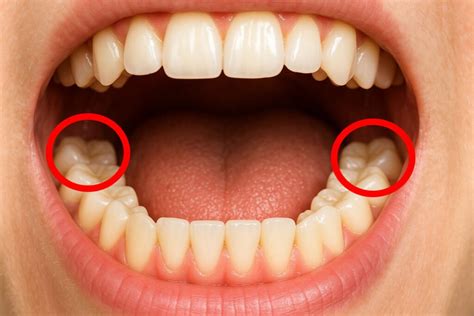

Las muelas del juicio son los últimos molares en aparecer en la boca, normalmente entre los 17 y los 25 años de edad. Estos dientes suelen aparecer entre los 17 y los 25 años de edad, aunque algunas personas nunca desarrollan las muelas del juicio. En total hay cuatro muelas del juicio o cordales, pero no todo el mundo las tiene todas. En ocasiones, únicamente emergen algunas de ella o incluso puede darse el caso de que no lleguen a salir y queden atrapadas en el hueso dental.

Muchas personas sufren la impactación de las muelas del juicio. Esto se produce cuando las muelas del juicio no tienen suficiente espacio para erupcionar en la boca o para desarrollarse normalmente. A veces, estas muelas no tienen suficiente espacio para salir correctamente y se quedan parcial o totalmente retenidas en el hueso o la encía. Para evitarlos, los odontólogos suelen recomendar la extracción de las muelas del juicio retenidas.